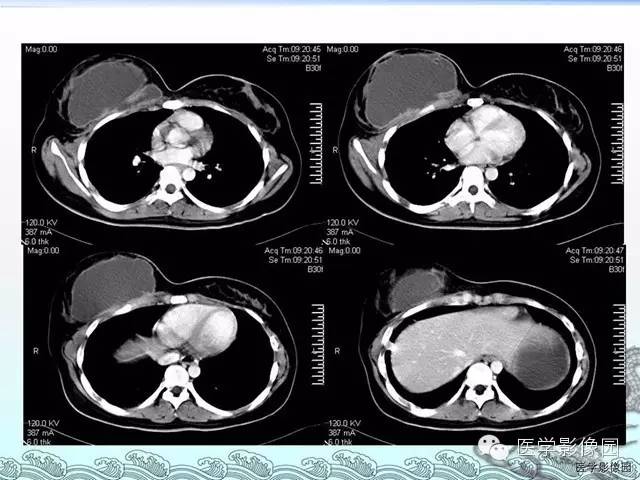

胸壁结核1例影像表现

【病例】胸壁结核1例影像表现